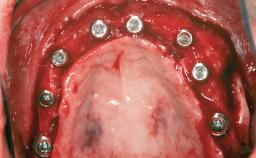

| # of Implants | 1 |

| Bone Augmentation | Staged|Vertical |

| Augmentation Materials | Autogenous chips|Membrane |